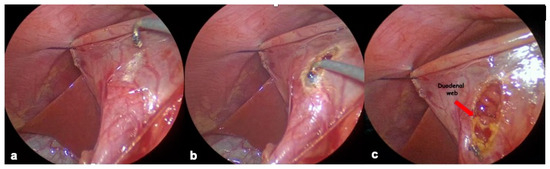

2.4.1. Endoscopic Resection

2.4.2. Laparoscopic Resection

2.4.3. Duodenal Web Localization